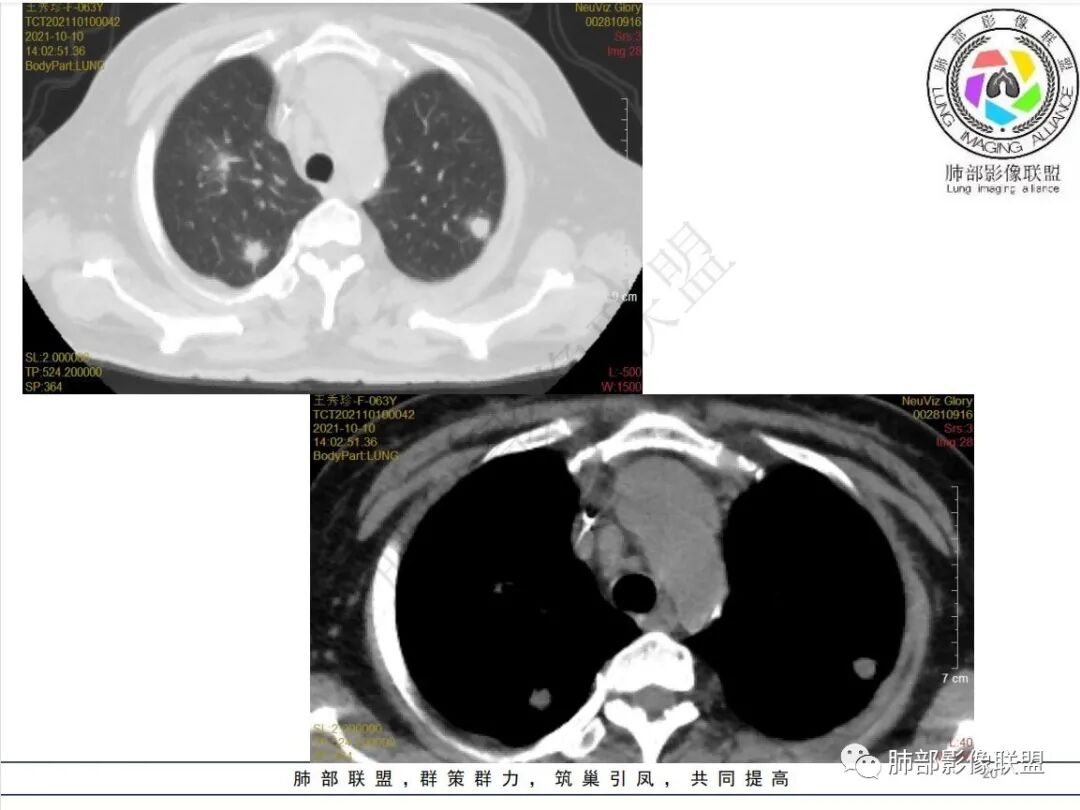

白血病病史,抗炎治疗后病灶明显增多,左肺有空洞并见液气平面,胸膜下楔形影,右肺有大片影,中心低外周密度高,符合血源性感染性病变,有位老师说过曲霉菌及结核属于干性坏死,不支持,毛霉和金葡都是液性坏死,本例有液气平面需要两者鉴别,从临床病史及影像进展情况看考虑支持毛霉菌感染,金葡一般进展比较快不支持,右肺动脉有侵犯,白血病肺侵润不知道有没有可能,工作中没遇到过,总之毛霉可能性较大,白血病肺浸润待排

老年女性,白血病史,粒细胞减少,肛周疼痛,高热,两肺多发结节,结节有晕征,治疗后肺内结节增多,并可见空洞,右肺门脓肿形成,右肺动脉受侵,纵隔内淋巴结肿大,白血病粒细胞减少常规思路,首先要考虑曲霉,曲霉在初诊治疗时,病变会增多,本例结节有晕,有血管侵蚀及胸膜楔形梗死灶,支持曲霉,有肛周疼痛,临床有发热,右肺门有脓肿,奴卡也要考虑

4.白血病化疗后,CT上出现多发结节,边缘可见晕征,病灶内可见多发坏死,右肺中叶肺动脉可见充盈缺损,右肺中叶可见融冰征,右肺中叶肺动脉侵犯栓塞伴右肺中叶肺梗死,可符合真菌感染。

6.肺曲霉病典型的CT表现是结节周围有磨玻璃样的晕征表现,或胸膜为宽基底的楔形实变。晕征表现为曲菌感染的肺结节伴梗死和凝固性坏死,周围有肺泡出血。最终可出现空泡征象,并可观察到中央坏死组织与周围肺实质分离形成空气新月征。